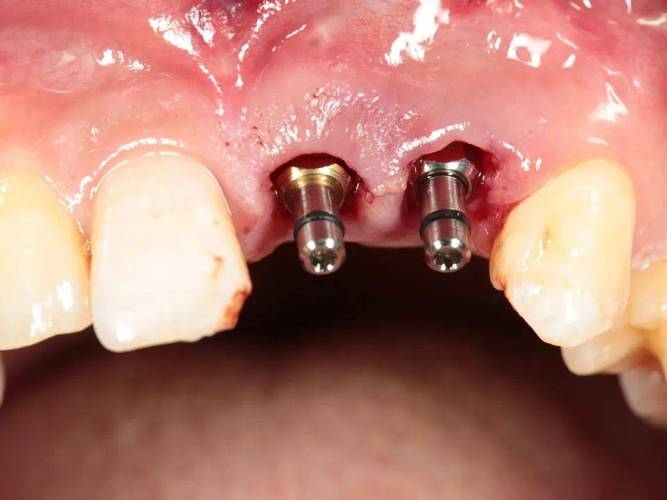

| 种植体植入 | 选择合适直径、长度的种植体,植入拔牙窝,确保种植体尖端位于牙槽骨 cortical 下3-5mm | 种植体与骨壁紧密贴合,初期稳定性良好(扭矩≥35N·cm),避免邻牙损伤 |

| 缝合与术后处理 | 无张力缝合拔牙创口,术后拍摄X光片确认种植体位置 | 嘱患者术后24小时内避免刷牙、漱口,服用抗生素预防感染,避免患侧咀嚼 |

术后需定期复查(术后1周、1个月、3个月),观察骨结合情况,一般3-6个月后,若种植体与骨组织结合良好(通过X光片或动度检测确认),可进行二期手术安装基台,再制作并佩戴牙冠,完成最终修复。